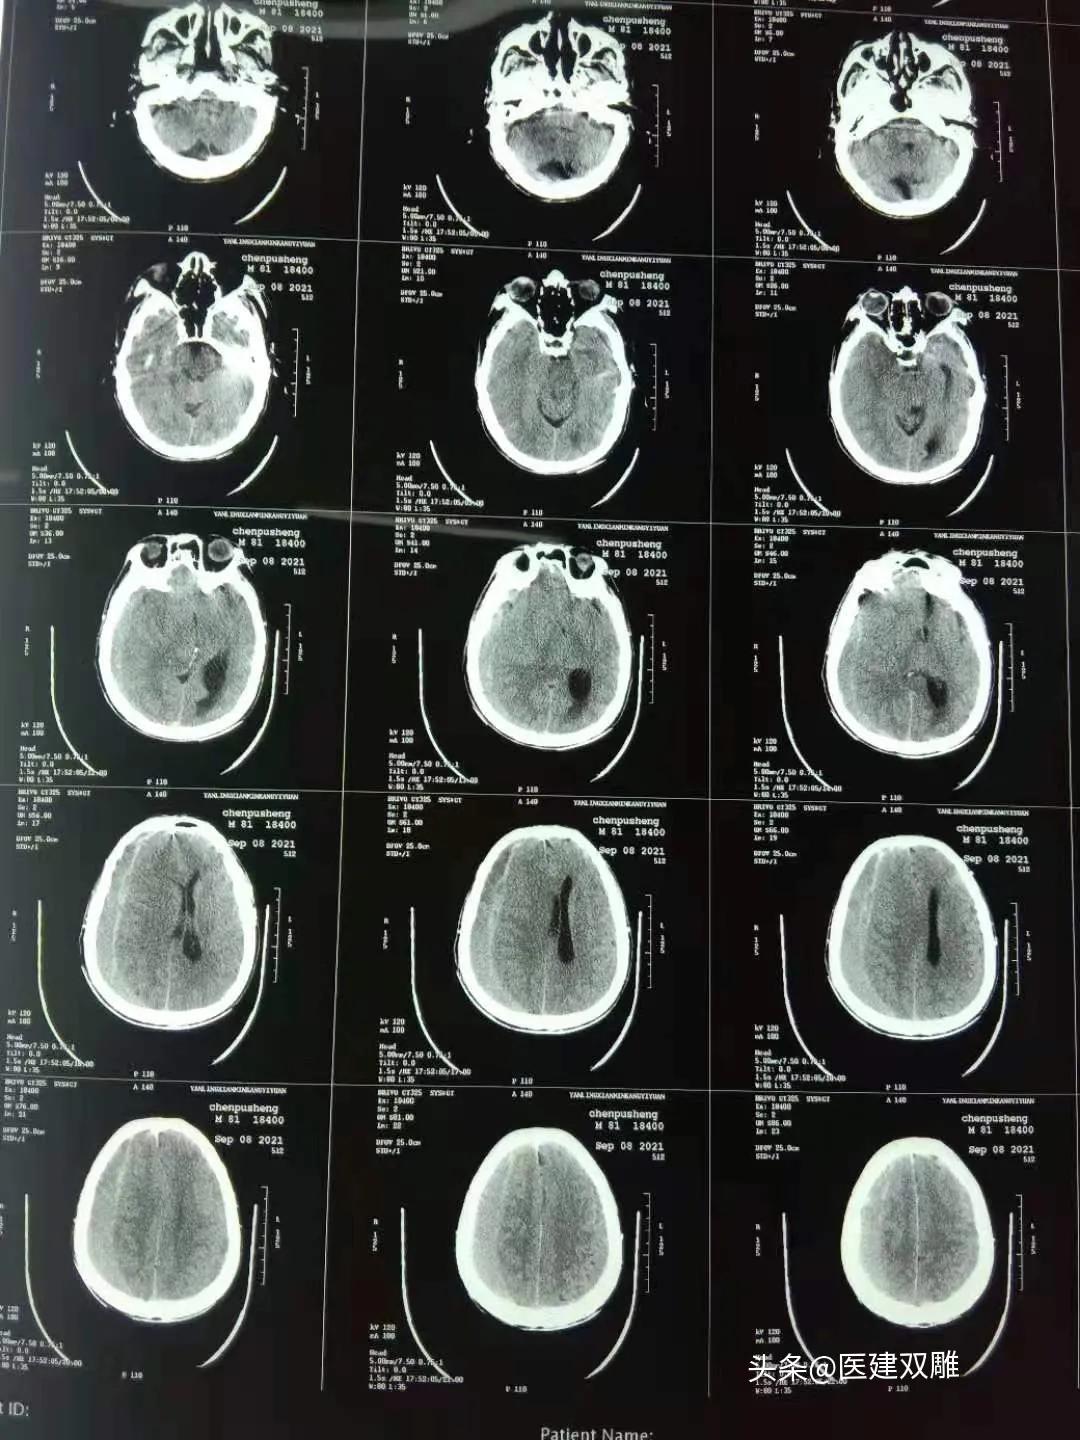

入院后即可完善心电图、常规生化、同时行头颅及肺部CT检查。头颅CT回报双侧硬膜下积液(血肿可能)、肺部同前,其他生化无明显异常。此刻、诊断明确转外科治疗,手术引流出暗红色不凝固的血性液体。术后患者恢复顺利。